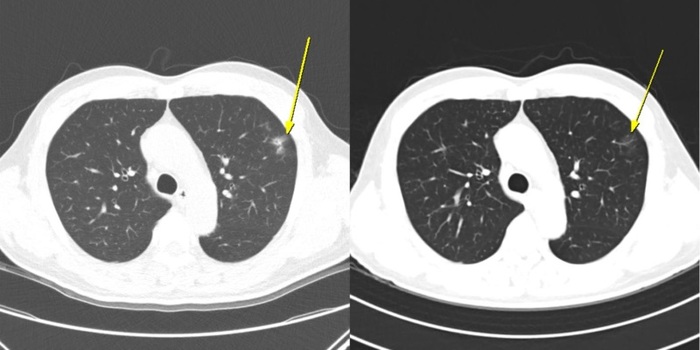

▲ 무증상 일시적 면역관련 폐렴 사례 = 이 환자는 AteBeva 치료 3개월째 시행한 저선량 흉부 CT(왼쪽)에서 폐 주변부에 미세 염증성 음영이 나타났으나, 6개월째 CT(오른쪽)에서는 자연적으로 소실되는 양상을 보였다. 치료는 지속됐으며, 이후 부분 관해(PR)를 달성했고 총 19.7개월간 무진행 생존(PFS)을 유지했다.